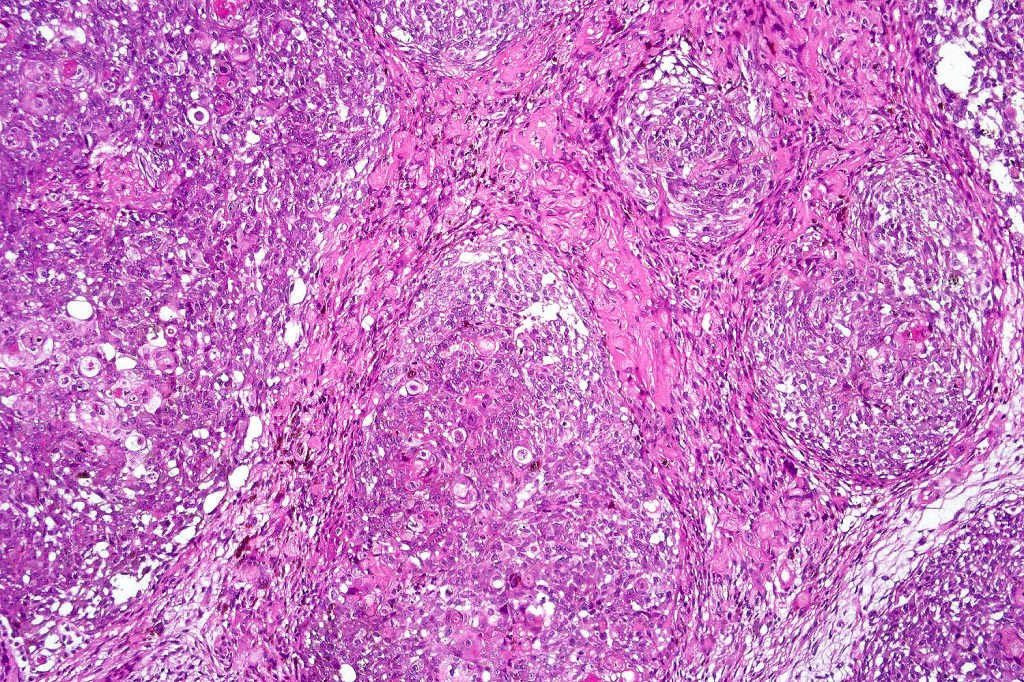

Histological features

•Usually well circumscribed

•Nodular or multinodular

•Basaloid population with prominent nucleoli accompanied by supramatricial and ghost cells

•Variable pleomorphism

•Mitoses may be conspicuous

•Heavily pigmented dendritic +/- epithelioid melanocytes

Often solar elastosis is marked